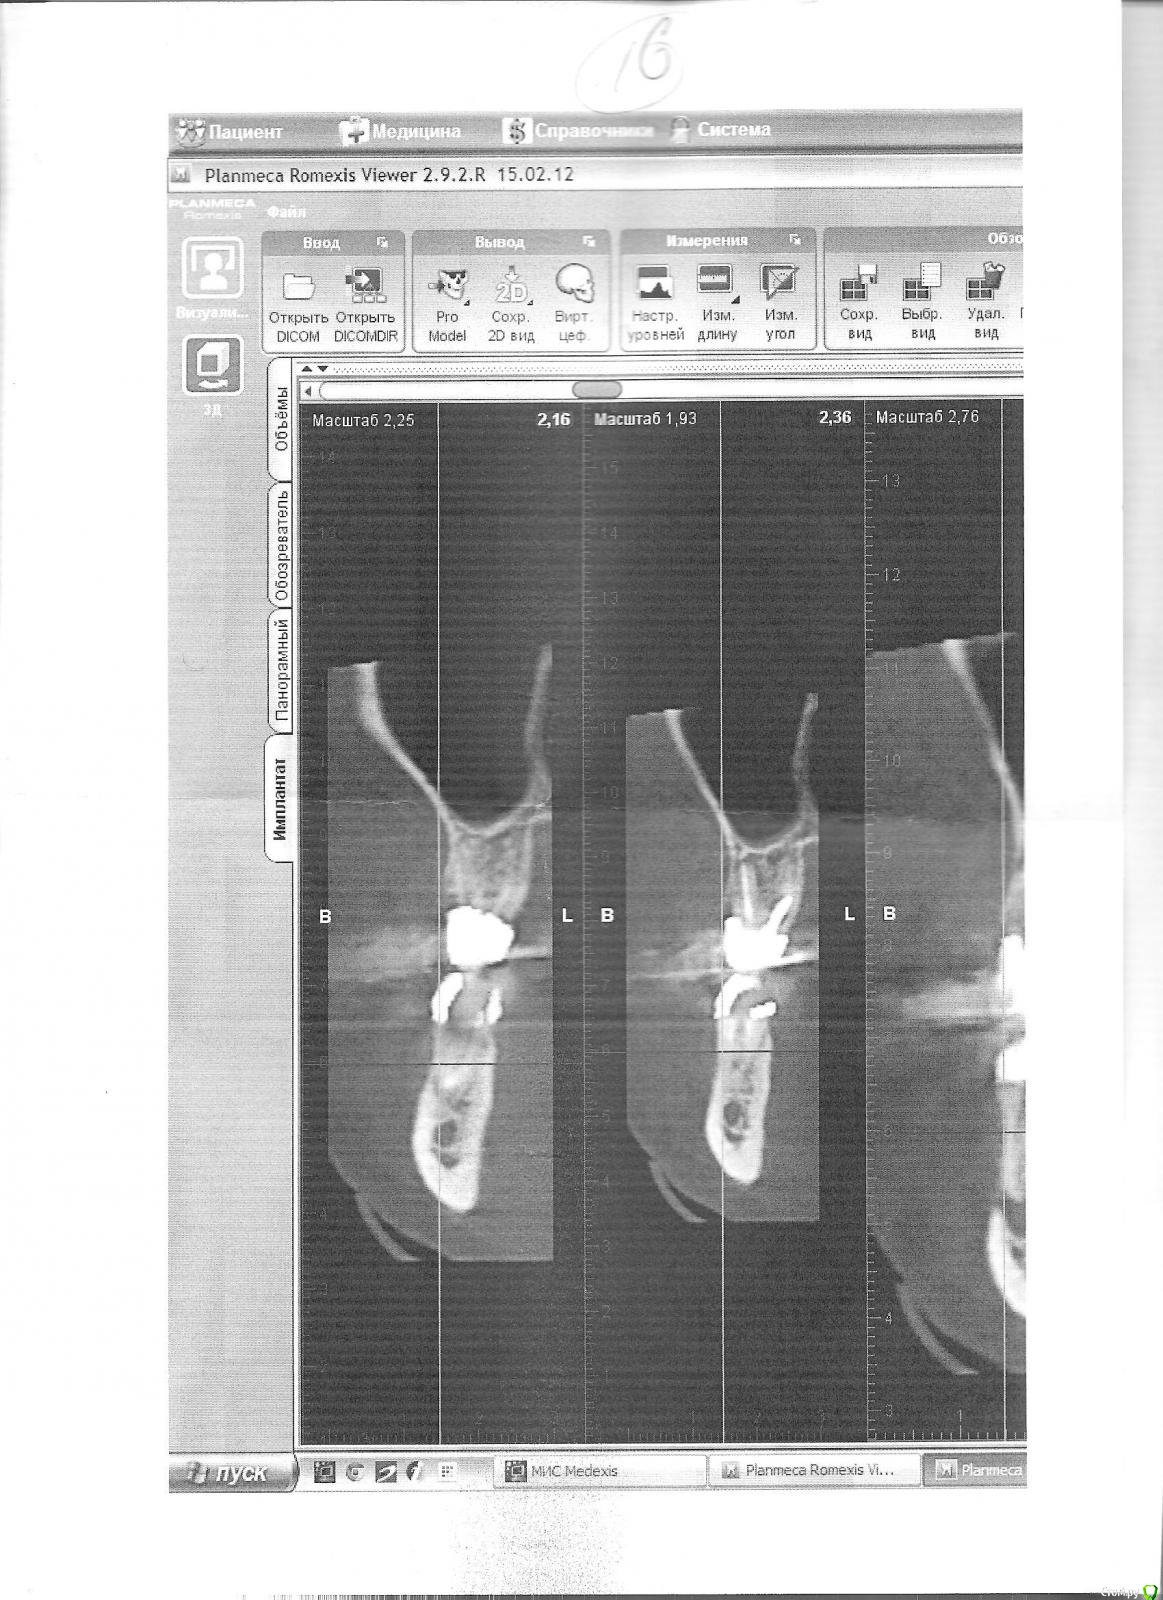

Возможно ли перелечить верхние шестерки? Срезы (если правильно называю) КТ прилагаются.

Проблемы вылезли на КТ, сделанном по другому поводу, эндо проверяли заодно, очередной прицельный снимок верхней левой (26?) врачу не слишком нравился. Сейчас, как мне сказали, на прицельном снимке  26 видно, что "мезиальный (так?) корень неспокоен" (пытаюсь цитировать). Прицельный снимок правой верхней шестерки (16?), сделанный после КТ, говорят, вообще воспаления не показывает. (Если эта информация была лишней, прошу прощения за многословие).